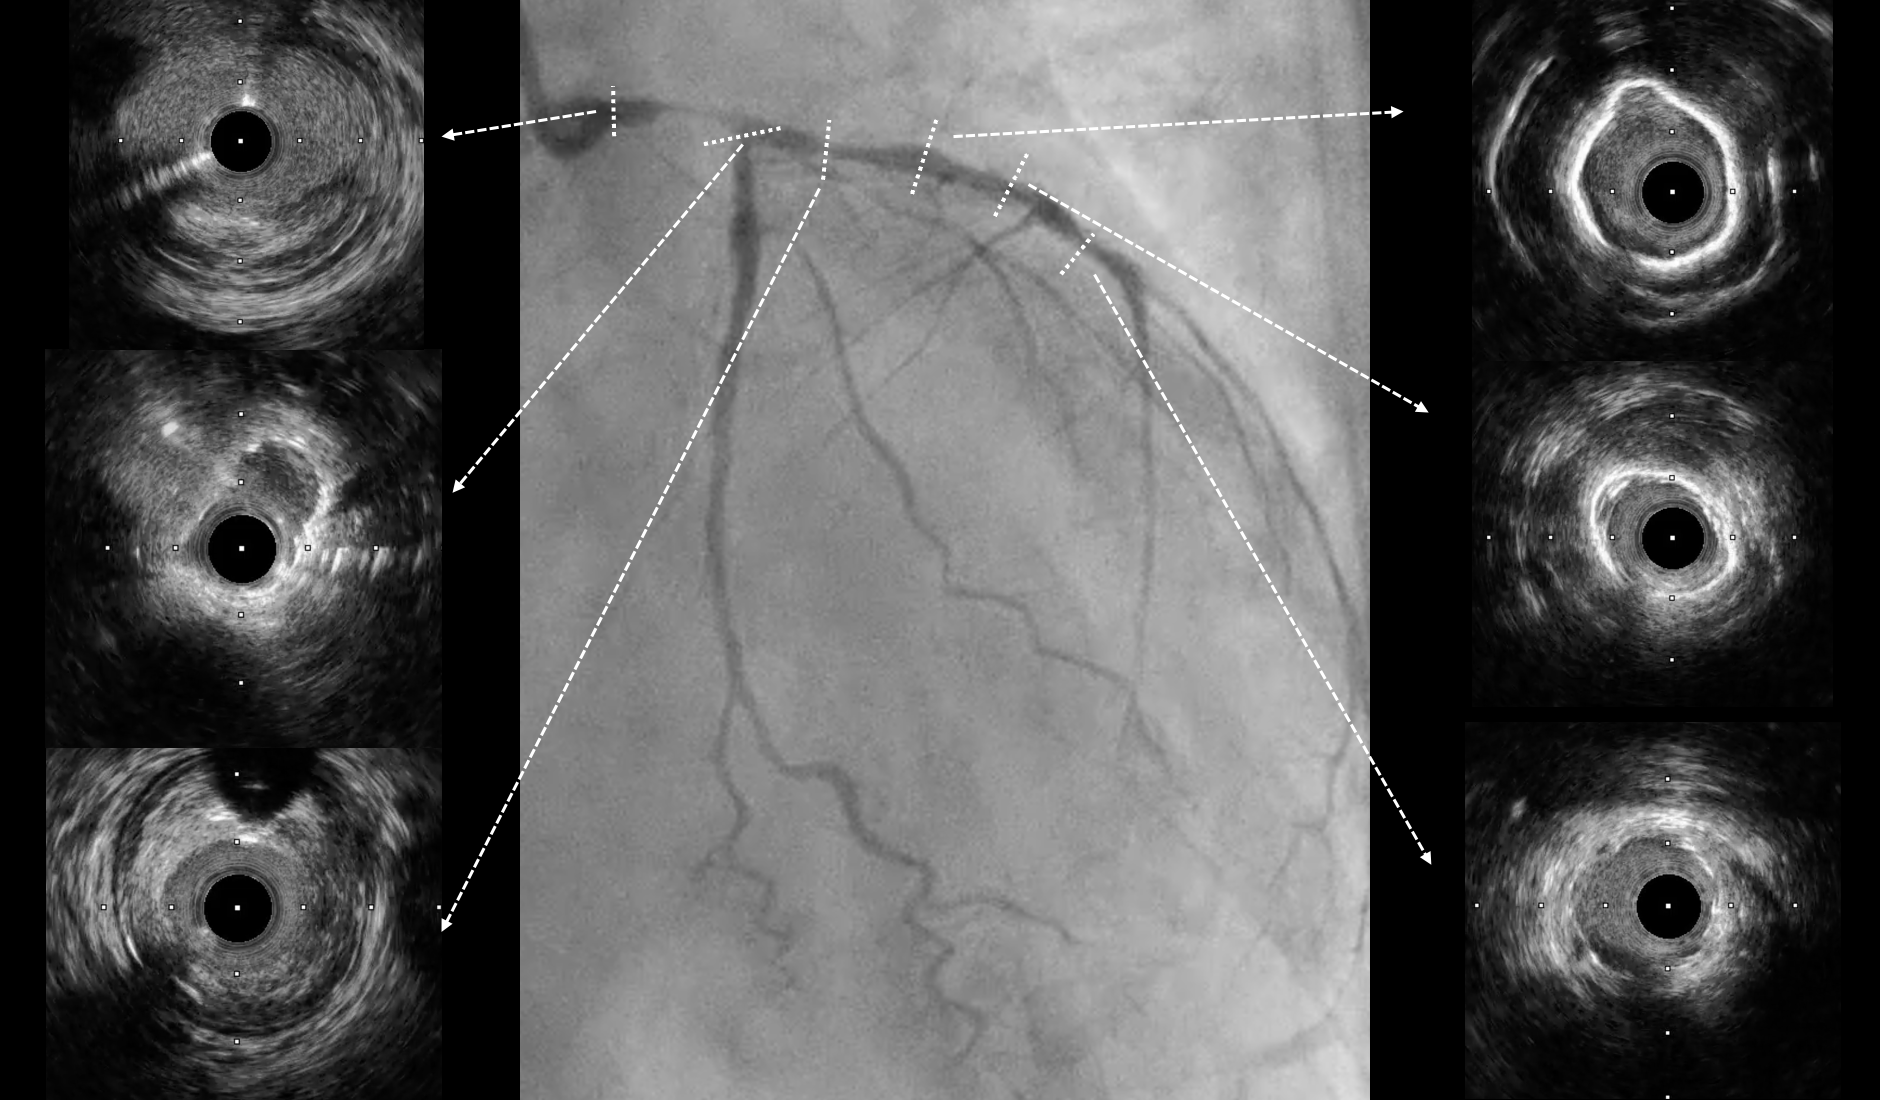

Severe CAD with LM + 3-vessel disease. dLM and shaft: critical stenosis; pLAD: critical stenosis; mLAD: s/p DES with stent underexpansion and proximal stent-edge restenosis; pLCX: s/p DES with proximal stent-edge restenosis; mRCA: 50% stenosis. SYNTAX score: 44.

Under IABP (left femoral), PCI via right brachial with 6 Fr EBU 3.5. Runthrough to LAD, Sion Blue to LCX. Predilation of LM/pLAD with 2.0¡¿20 mm balloon; IVUS pullbacks. Further dilatation with 2.5¡¿20 mm NC for mLAD underexpansion, pLAD, and LM. oLCX de novo and pLCX edge ISR predilated with 2.5¡¿20 mm NC; LCX ISR treated with DCB 2.5¡¿20 mm. Szabo technique attempted for LM–LAD with a 3.0¡¿24 mm DES; the undeployed stent dislodged during repositioning and was deployed at the dislodgement site. IVUS showed 2–3 struts protruding into the aorta from the LM ostium and incomplete pLAD coverage. Post-dilation with 3.5¡¿20 and 2.5¡¿20 mm NC; DCB 3.0¡¿20 mm for pLAD uncovered plaque and mLAD proximal edge ISR. Final CAG: TIMI 3 flow.At 3 months, staged PCI via right radial with 6 Fr EBU 3.5. Sion Blue ES to distal LAD. IVUS: mLAD stent underexpansion (MSA <2.0 mm©÷); wire not through struts. IVL 3.5¡¿12 mm initially could not cross LM; after guide exchange (JL 3.5, then EBU 3.0/3.5), IVL advanced to mLAD and delivered 100 shocks, producing a ring crack and area gain. Further dilation with 3.0¡¿20 and 3.5¡¿20 mm NC. IVUS: pLAD type B dissection without flow limitation. DCB 3.5¡¿40 mm to p–mLAD. LM ostial stent further dilated with 3.5¡¿20 mm. Final CAG: TIMI 3 flow.